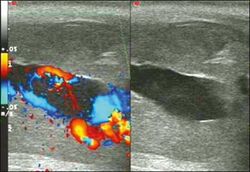

Venous drainage is performed by the deep and superficial dorsal veins of the penis. The dorsal arteries of the penis are located adjacent to the deep dorsal vein and a cavernous artery is located in the center of each corpus cavernosum. On color Doppler, the cavernous arteries present single phase flow. In the flaccid penis (Figure 3), the normal cavernous arteries show a systolic peak between 11 and 20 cm/s. At the beginning of erection, the systolic and diastolic flows undergo progressive increases. When vein occlusion begins, the diastolic flow decreases progressively, and once stiffness is established, it becomes negative.[1]

Priapism is defined as a painful and prolonged penile erection, with or without sexual stimulation. Color Doppler ultrasound is the imaging method of choice for the investigation of priapism, because it is noninvasive, widely available, and highly sensitive. By means of this method, it is possible to diagnose priapism and differentiate between its low- and high-flow forms.[1]